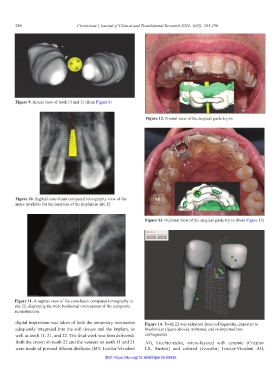

Figure 9. Apical view of teeth 13 and 11 (from Figure 8)

Figure 12. Frontal view of the surgical guide try-in

Figure 10. Sagittal cone-beam computed tomography view of the

space available for the insertion of the implant in site 12

Figure 13. Occlusal view of the surgical guide try-in (from Figure 12)

Figure 11. A sagittal view of the cone-beam computed tomography at

site 22, displaying the wide horizontal overcontour of the composite

reconstruction